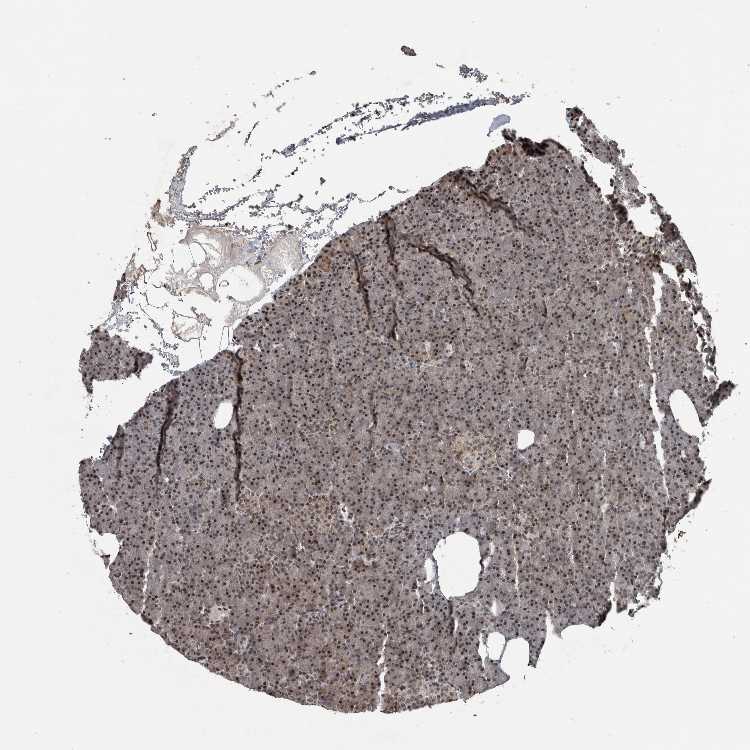

Antibody HPA027009

Exocrine glandular cells High

Pancreatic endocrine cells Low